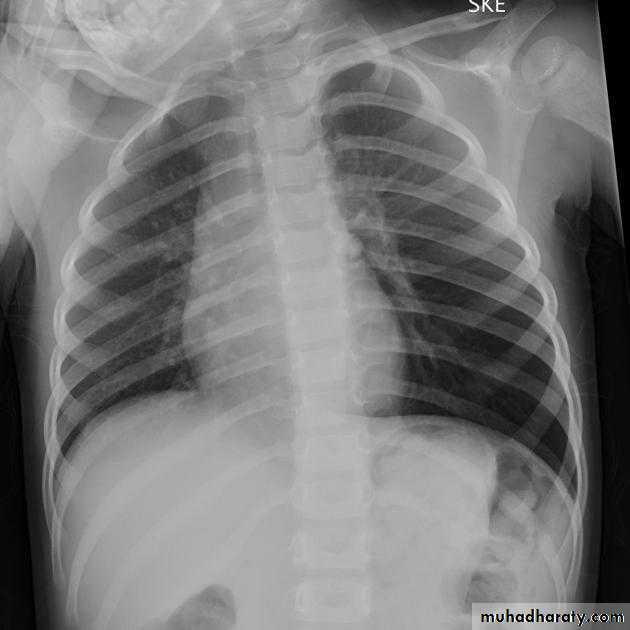

Unilateral obstructive emphysemaunilateral emphysema or atelectasis are the most common findings; only uncommonly will a radio-opaque foreign body be demonstrated ,Aspirated foreign bodies have a predominance for the right tracheo bronchial tree.

Pulmonary bullae are focal regions of emphysema with no discenible wall which measure more than 1cm in diameter